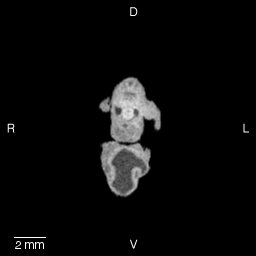

Stage 16 (Day 37), transverse slice 12